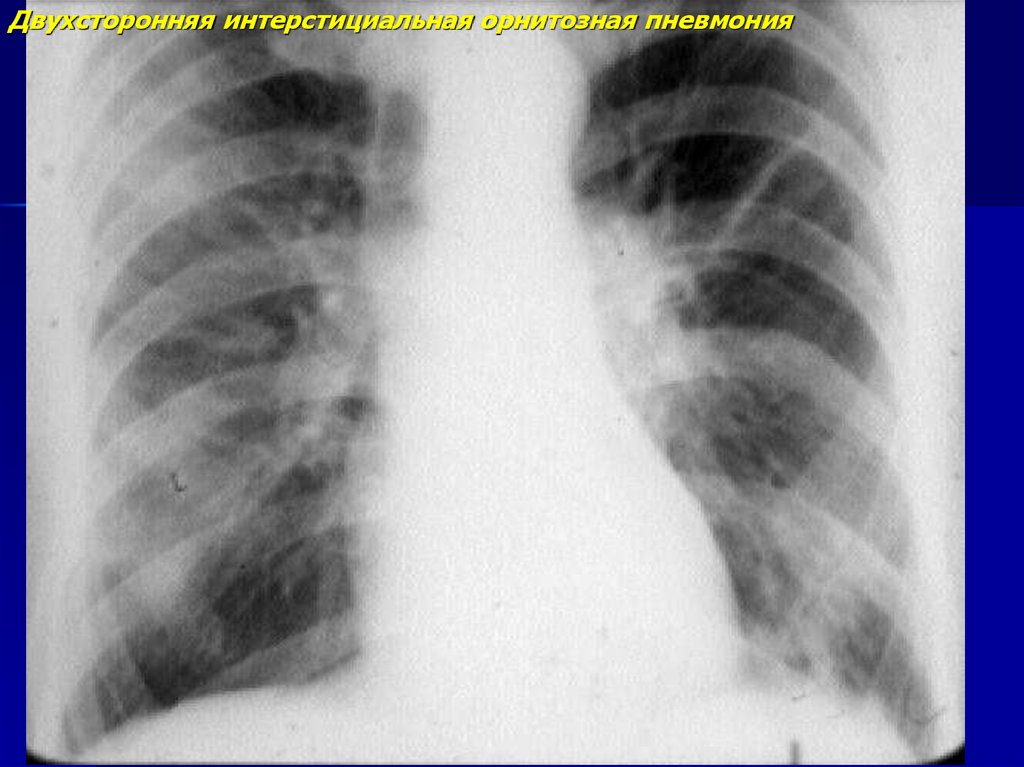

Двухсторонняя интерстициальная орнитозная пневмония